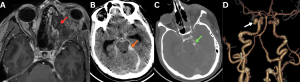

Fig 13: Clinical history:

A 56-year-old diabetic male with known invasive fungal sinusitis presented with sudden-onset severe headache, vomiting, and altered consciousness.

Figure A:

Axial post-contrast T1-weighted MRI image demonstrates heterogeneously enhancing soft tissue extending from the left ethmoid air cells into the left orbit (red arrow).

Figure B:

Axial non-contrast CT brain image demonstrates acute subarachnoid hemorrhage predominantly involving the basal cisterns (orange arrow).

Figure C:

Axial contrast-enhanced CT (CECT) brain image demonstrates a well-defined contrast-filled outpouching in the left prepontine cistern (green arrow), suspicious for an intracranial aneurysm.

Figure D:

Reconstructed CT angiographic image demonstrates a saccular aneurysm arising from the left superior cerebellar artery (white arrow).